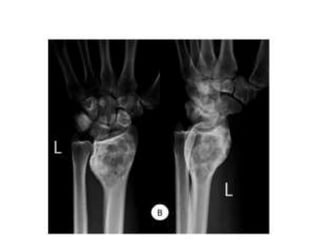

JULY 2009

SEPT 2009

1 year later

CASE 1

CASE 2

CASE 3

CASE 4

CASE 5